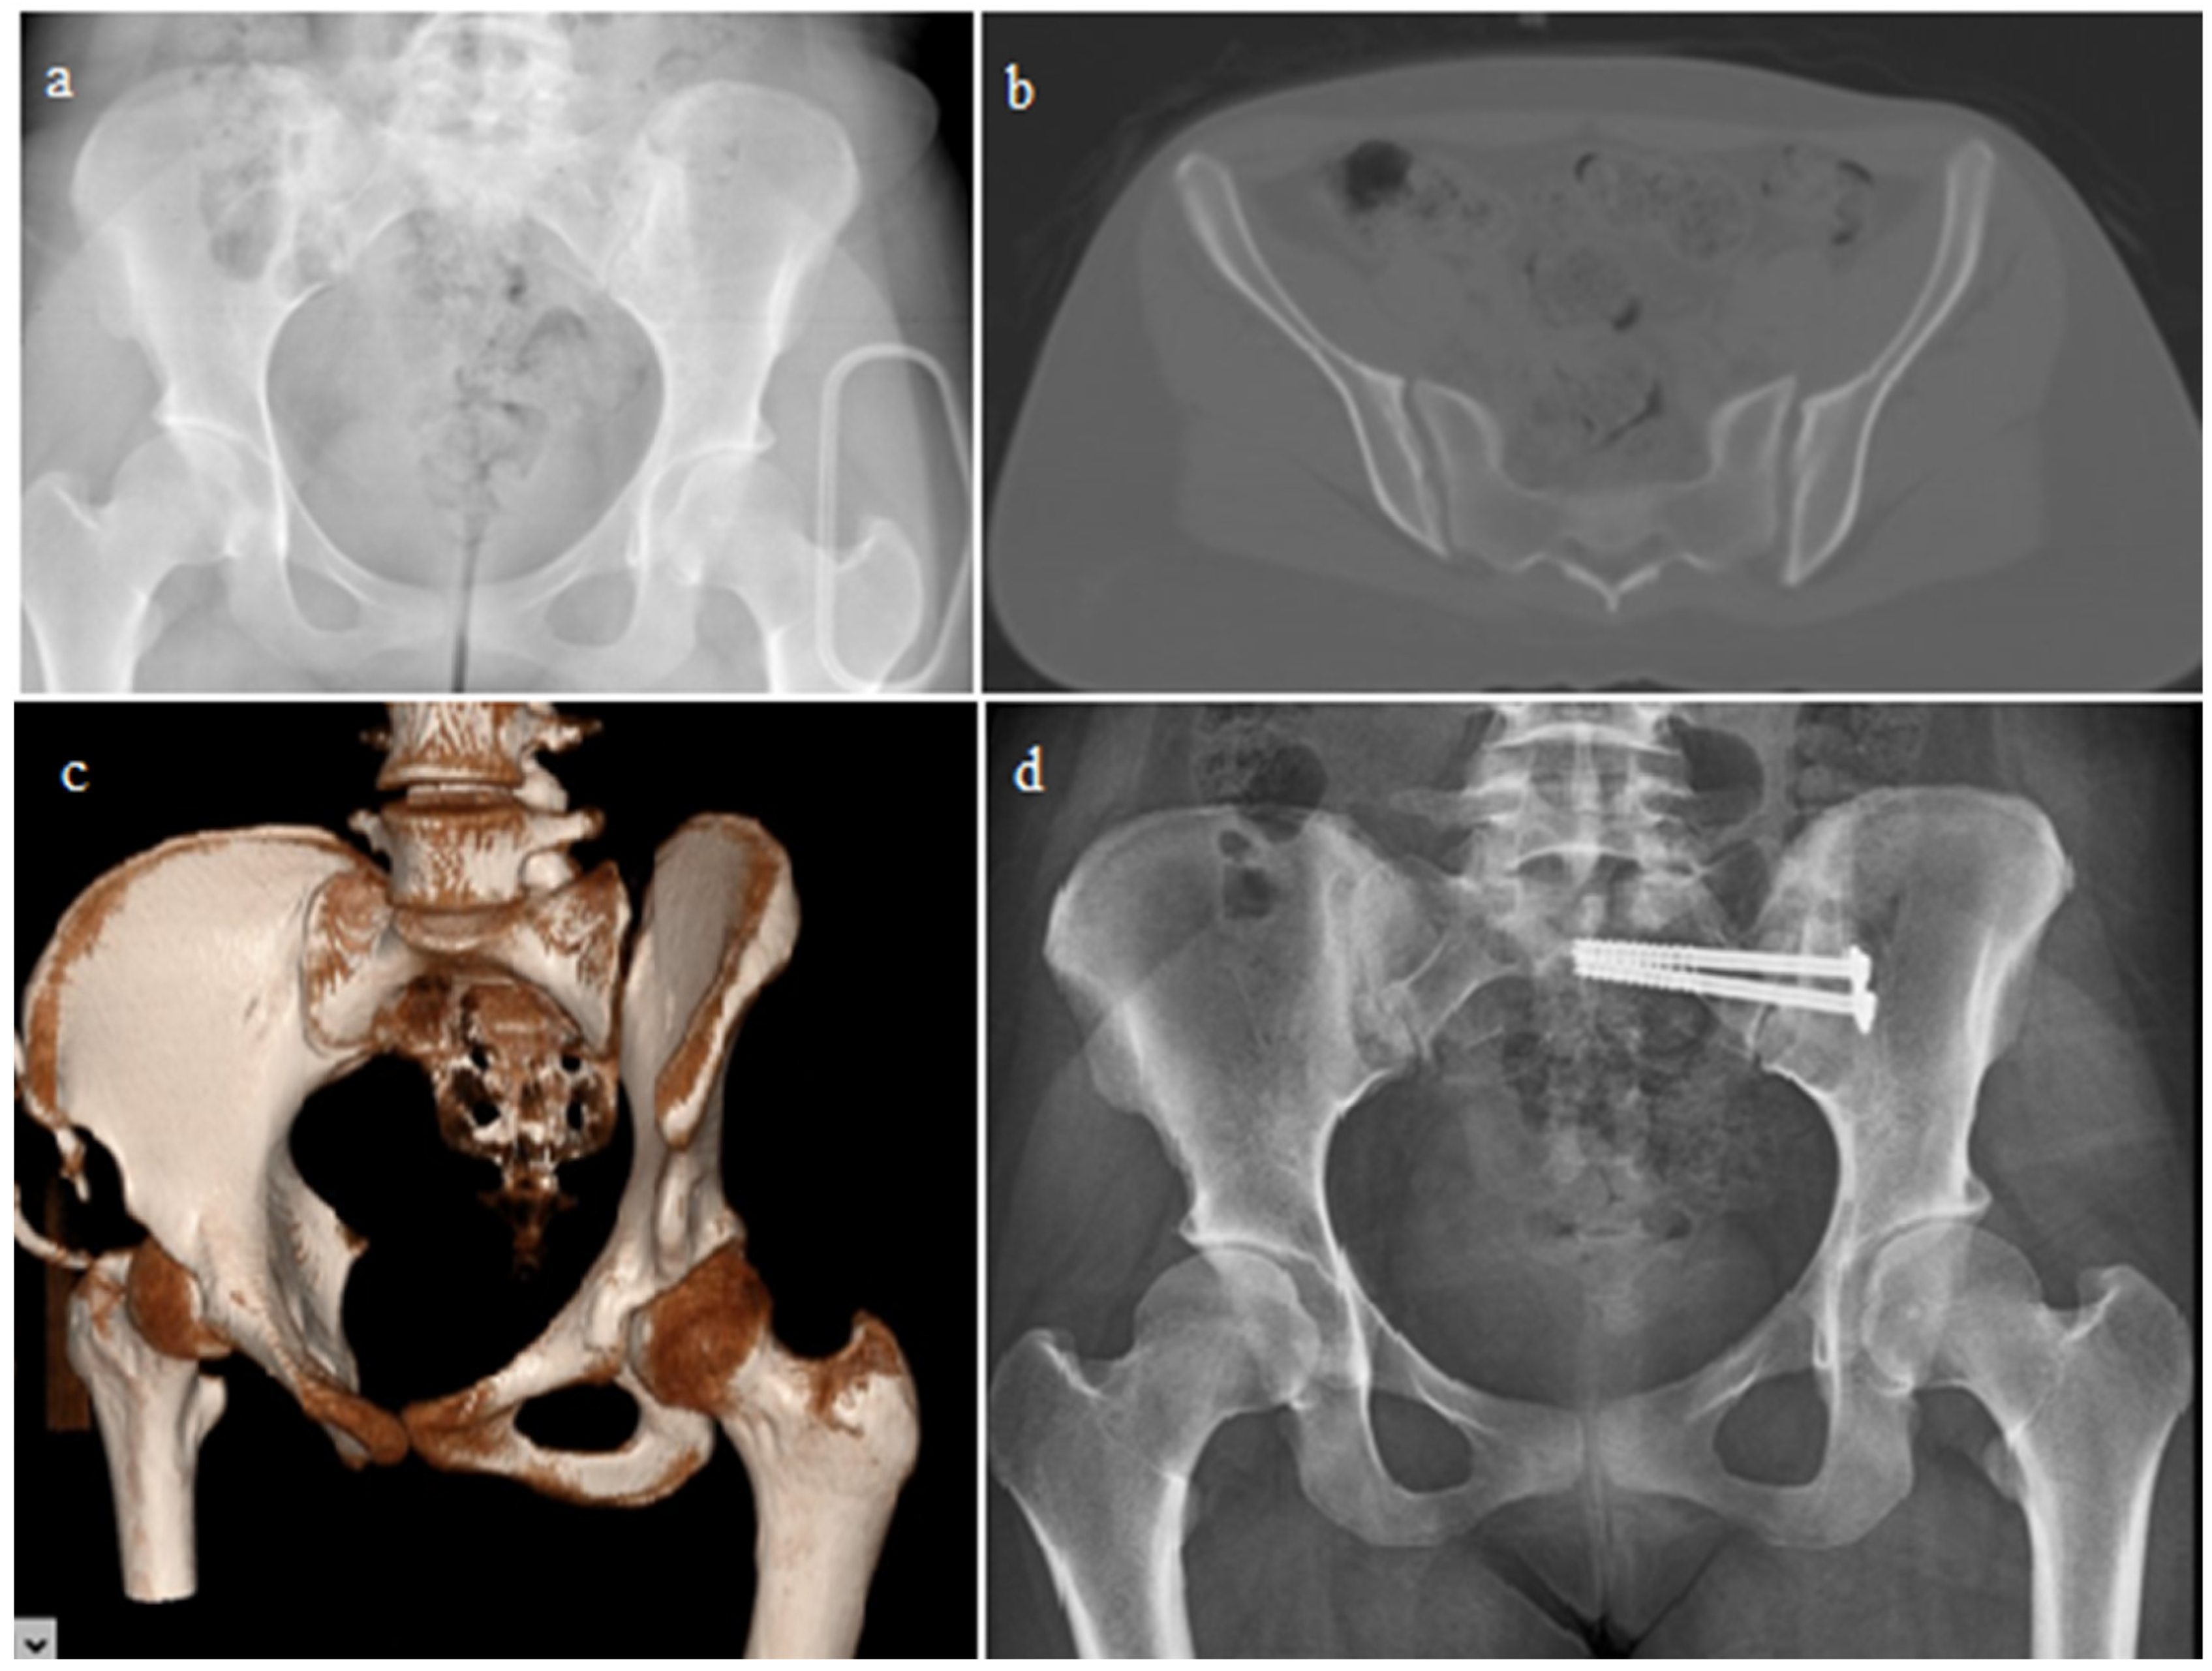

| Closed reduction + ISS | 59 | 48.7 |

| Open reduction + Anterior PS | 36 | 29.75 |

| Open reduction + Posterior PS | 15 | 12.4 |

| Open reduction + ISS | 11 | 9.1 |